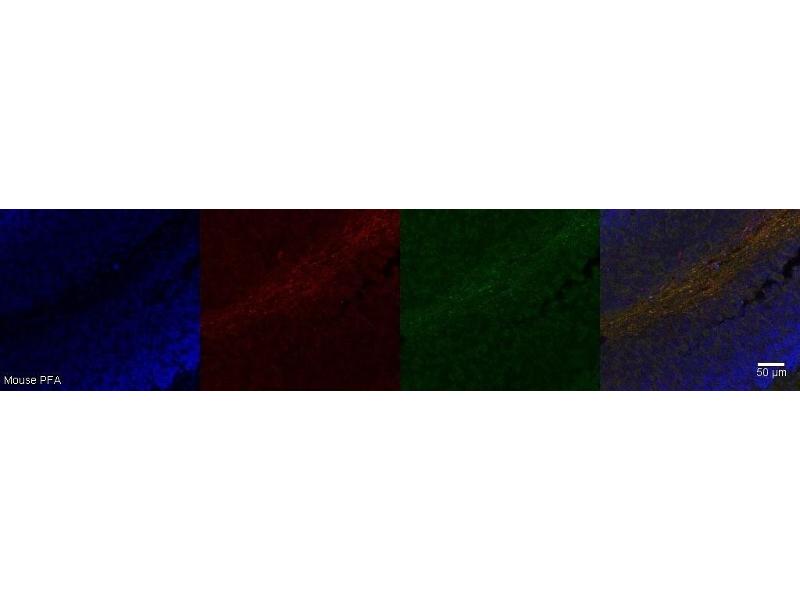

FAM107A Antikörper

Der Maus Monoklonal anti-FAM107A Antikörper wird verwendet zum Nachweis von FAM107A in Proben von Human und Maus. Er wurde validiert für IHC.

Immunohistochemistry (IHC)